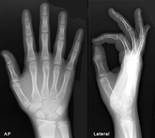

Рис.10. Нормальные кости: 1 – подростка; 2, 3 – взрослого.